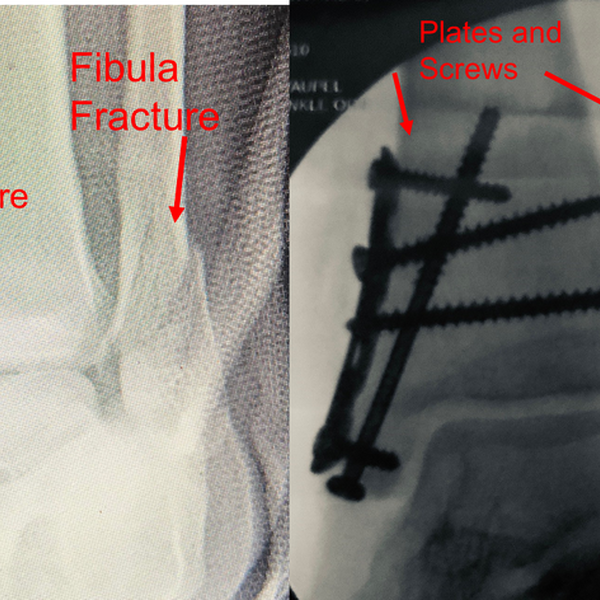

Zachary Vaupel Vaupelmd Twitter